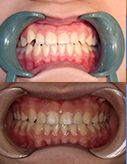

矫正牙齿不容易,矫正完成更珍惜